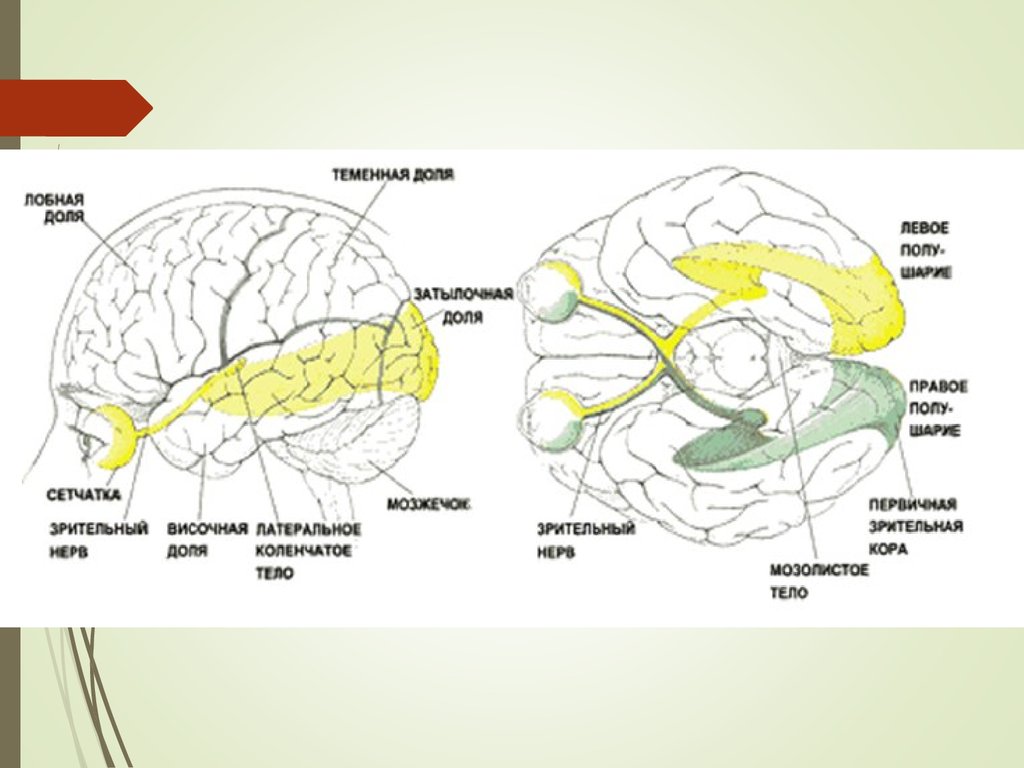

Схема чувствительных зон новой коры мозга